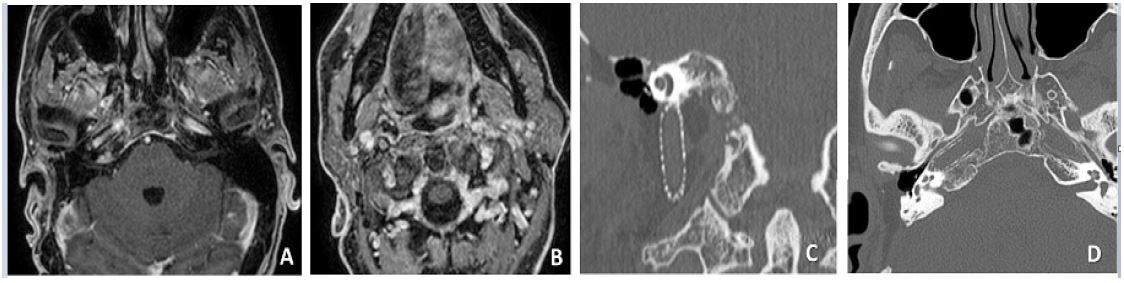

The last contrast-enhanced MRI and HRCT scans (October 2021) demonstrated patency of the right ICA with the intraluminal stenting in place and no signs of tumor recurrence (Figure 2).

Figure 2: (A,B,C,D): No residual or recurrent tumor can be appreciated on post-operative Gd-enhanced MRI scans (A,B). Post-operative HRCT shows intraluminal stenting from the neck (C) to the horizontal petrous (D) portions of the ICA.